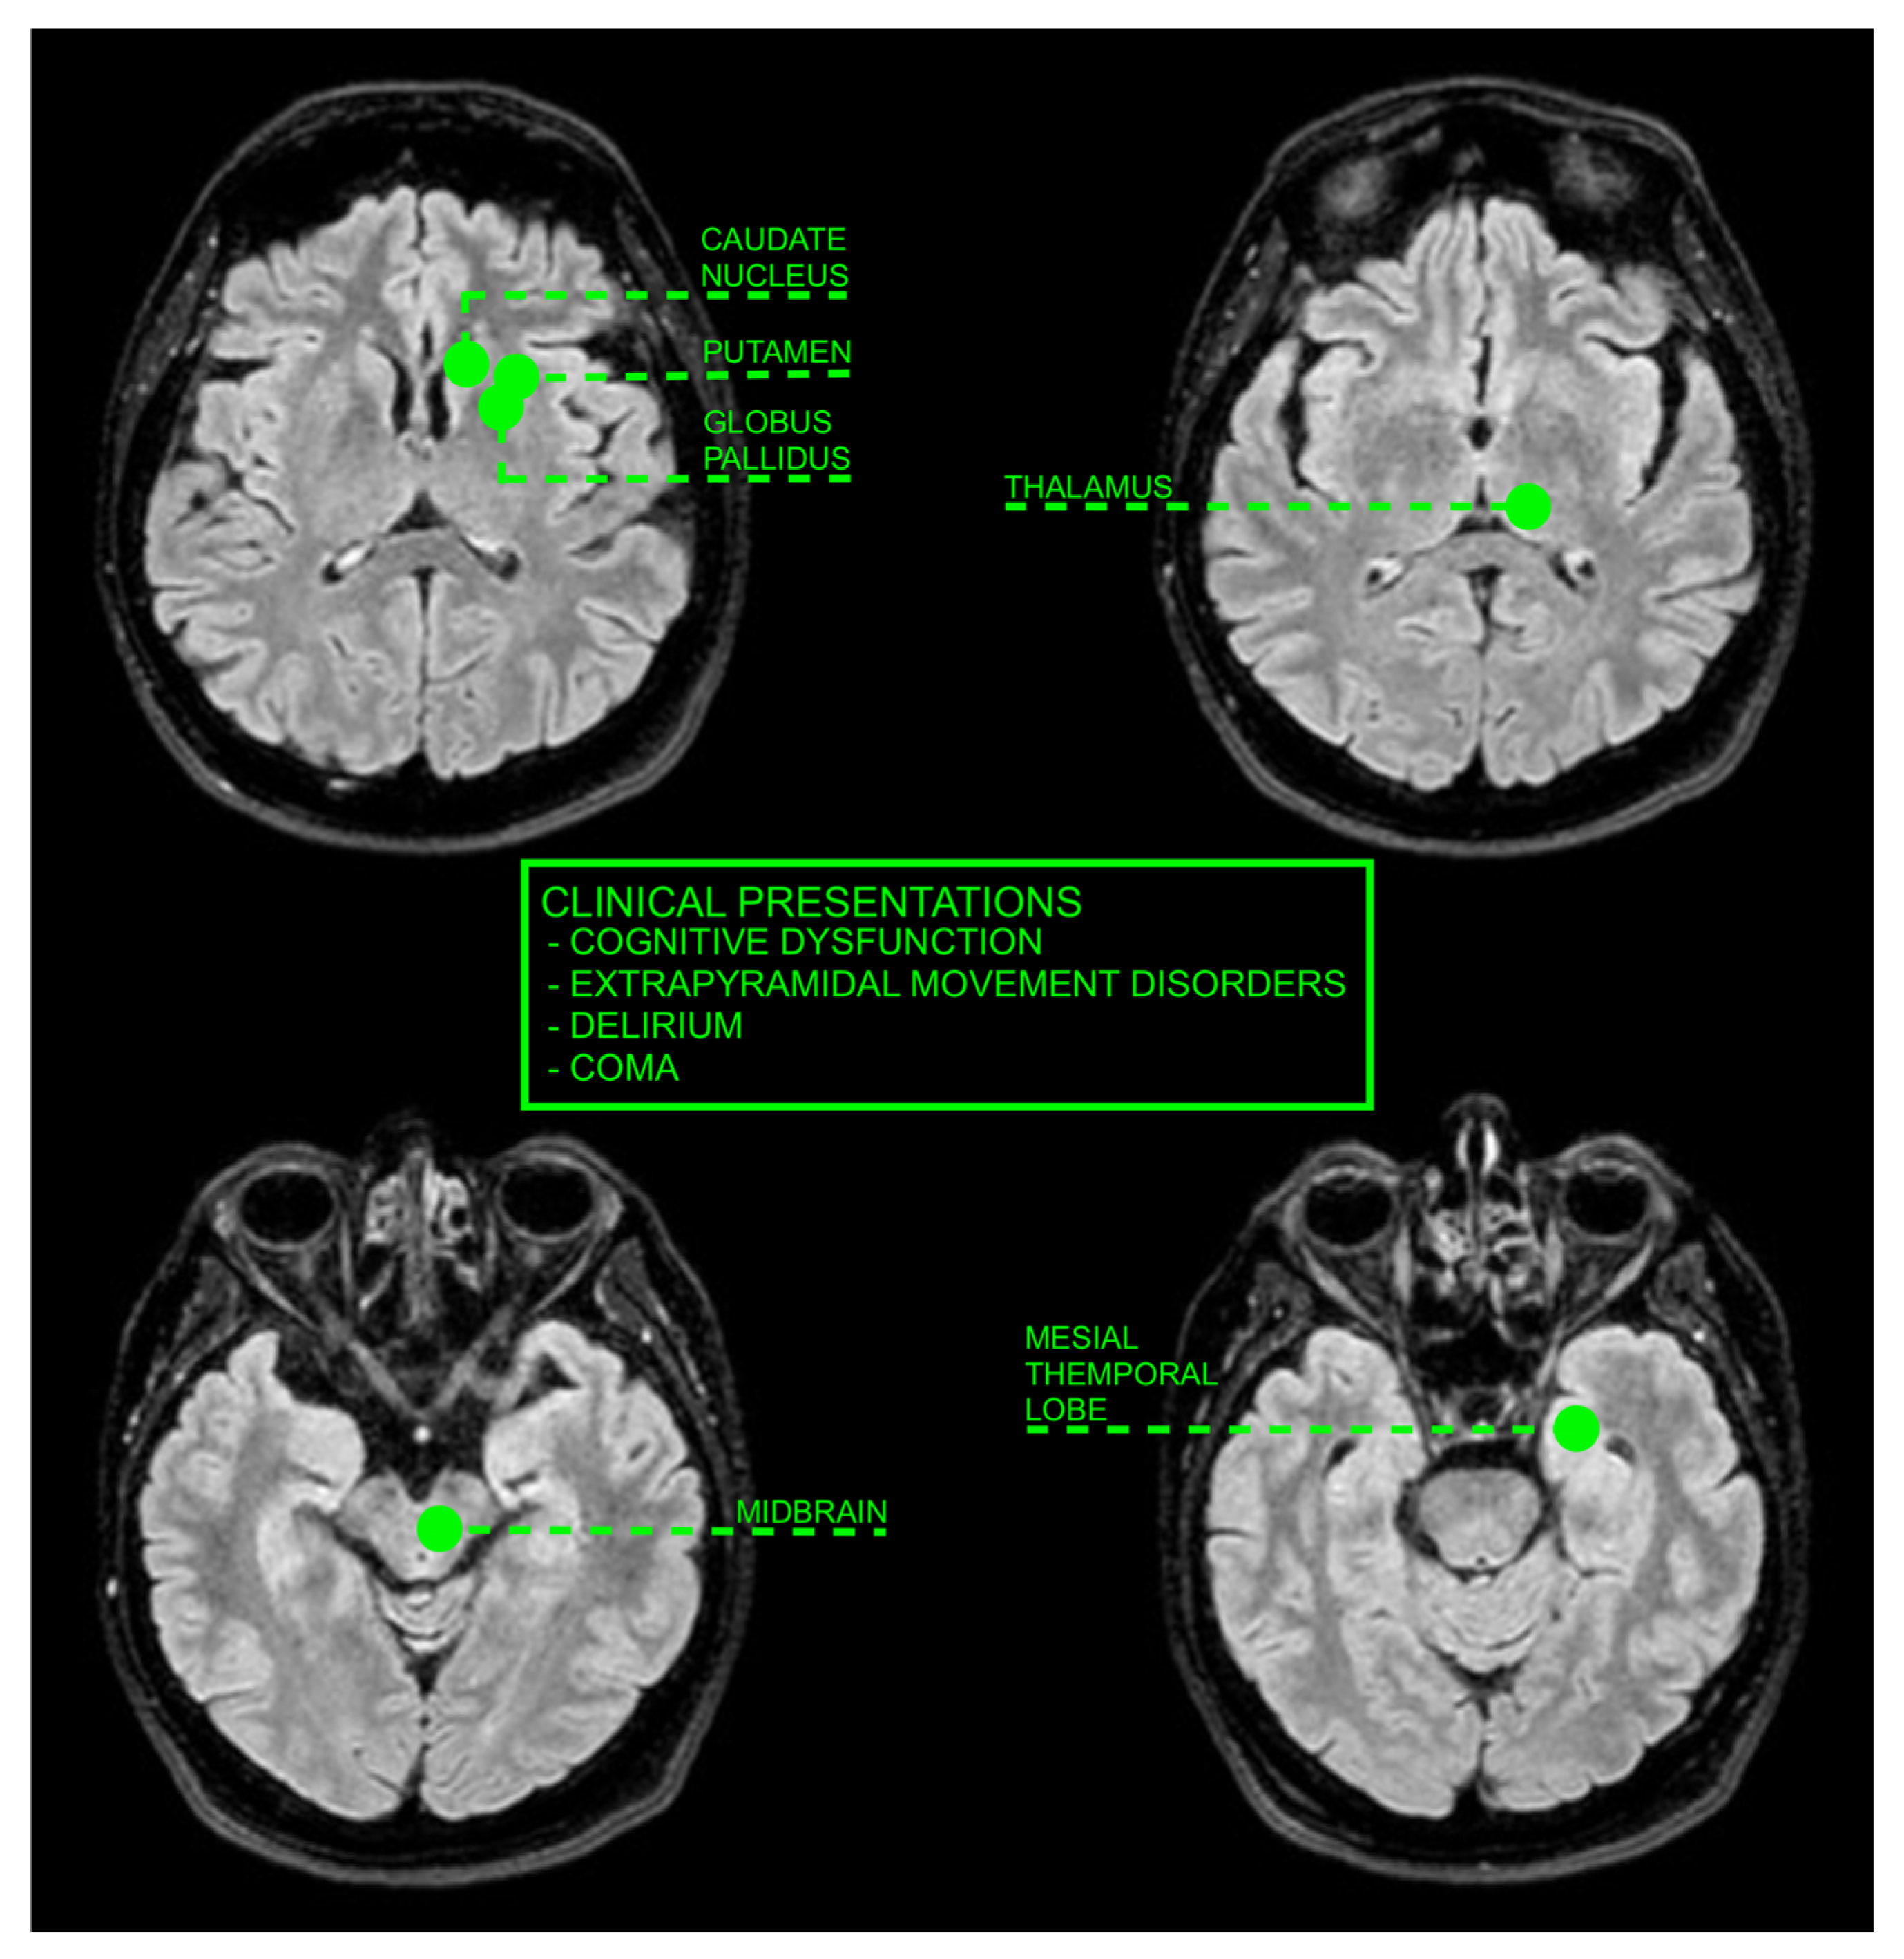

| Wang et al. [19] | 2003 | Taiwan | Clarify the clinical spectrum and possible pathophysiology of UE with BG involvement | 6 | BG lesions in uremic patients are associated with acute movement disorders and are not uncommon. The pathophysiology remains unclear. |

| Lee et al. [20] | 2007 | Republic of Korea | Investigate acute bilateral BG lesions in diabetic uremic patients | 4 | Bilateral BG lesions are primarily vasogenic, with some foci of cytotoxic edema. Lesions and symptoms are reversible post-hemodialysis. |

| Wang et al. [21] | 1998 | Multiple | Report on acute and subacute extrapyramidal movement disorders in uremic patients with BG lesions | 3 | UE with BG lesions leads to movement disorders and is linked to hypoperfusion and toxin vulnerability of the BG. |